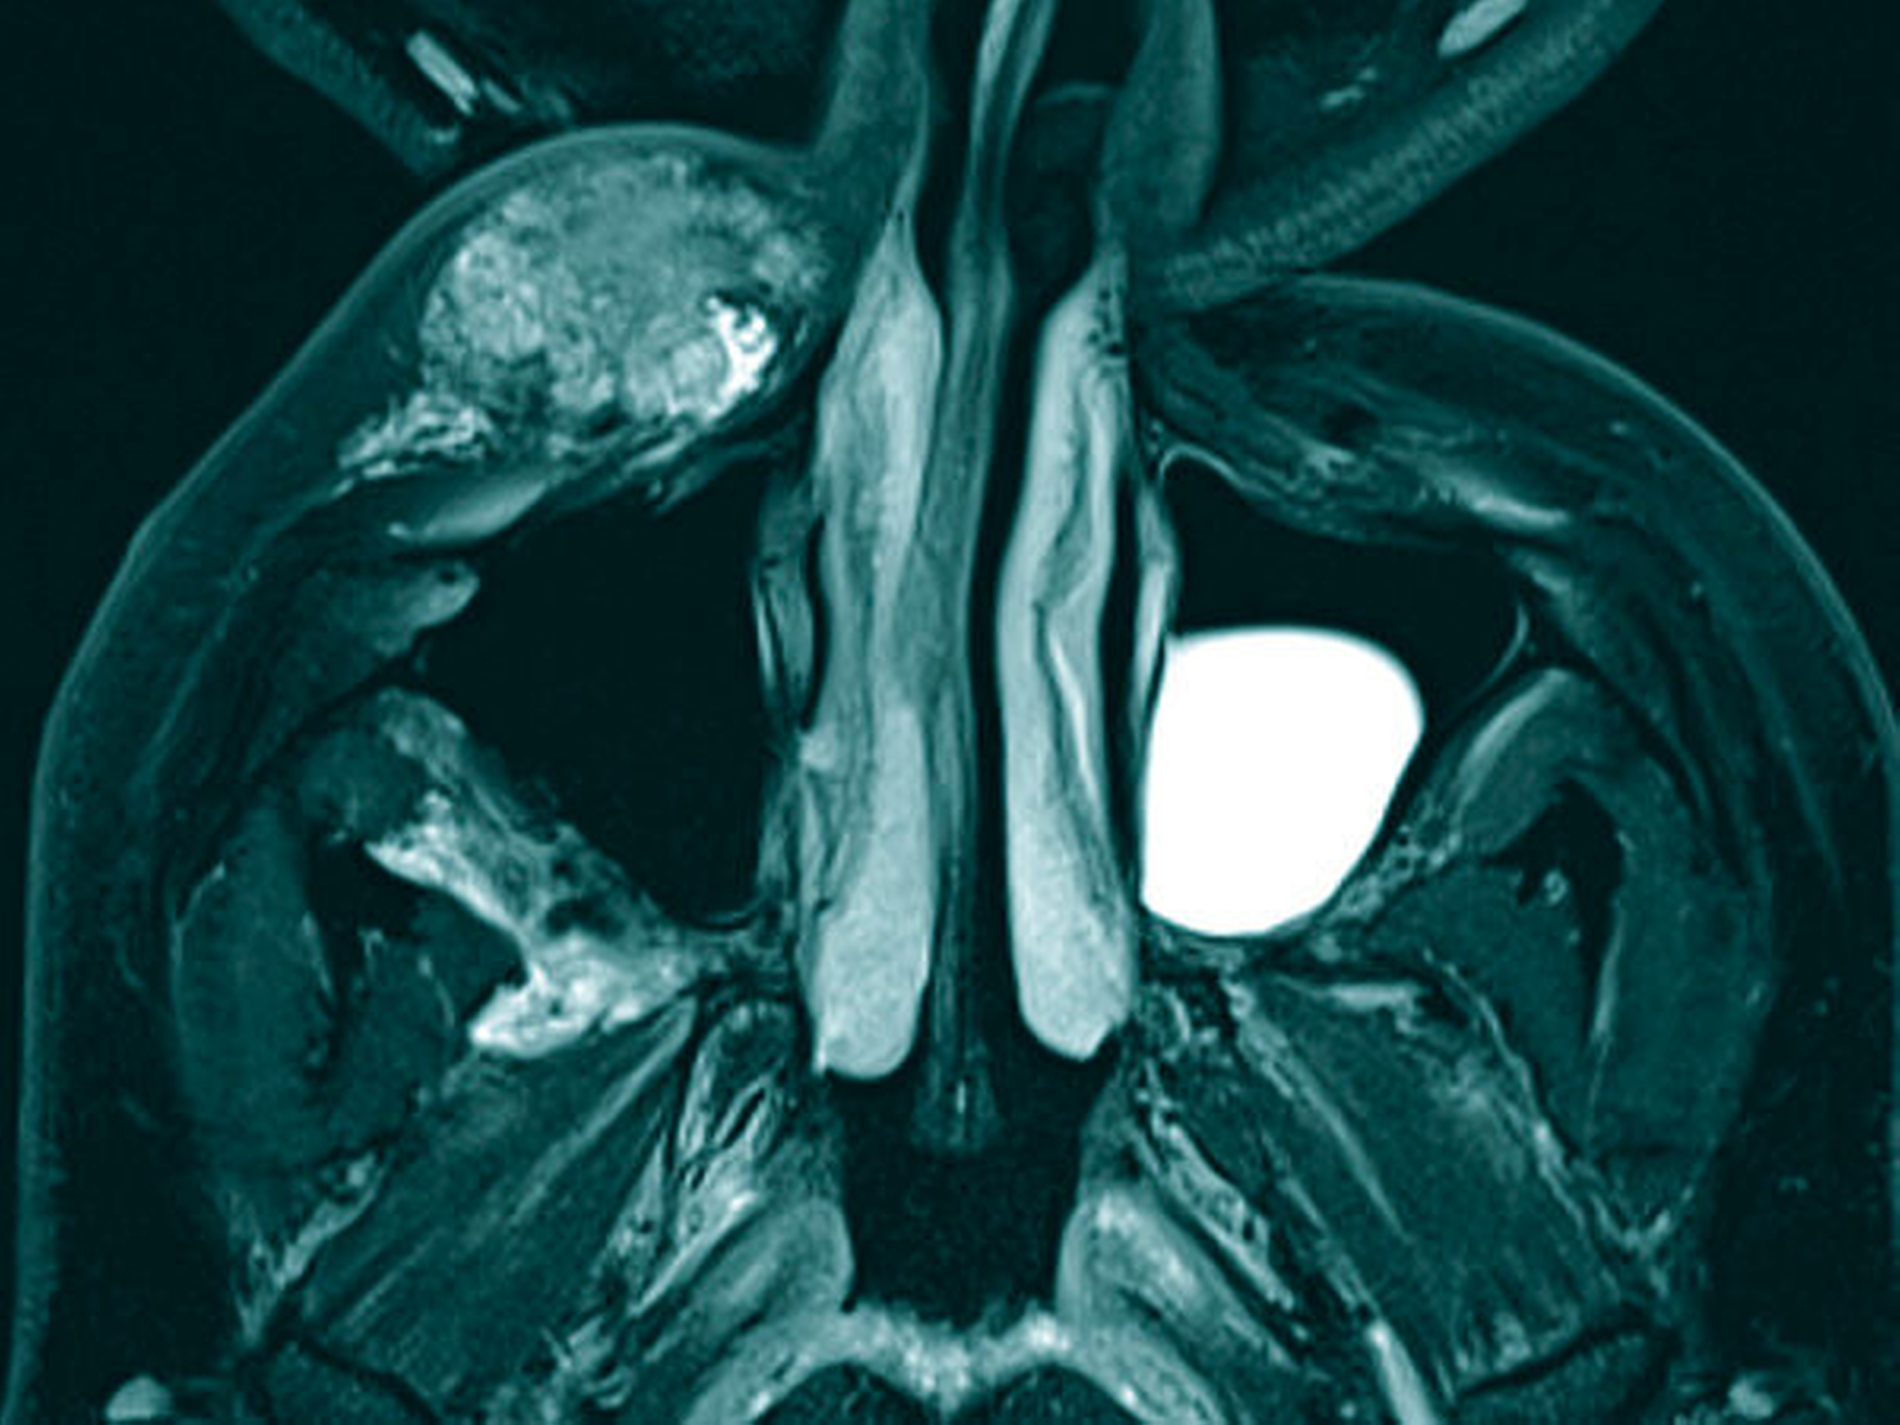

Zur Beurteilung der Befundausdehnung und zur Planung der Therapie wurde präoperativ eine Magnetresonanztomografie (MRT) des Schädels angefertigt (Abbildung 2). Hier zeigte sich die bekannte vaskuläre Malformation der rechten Wange mit Ausläufern nach intraorbital, in die Fossa pterygopalatina und infratemporalis. Im Vergleich zu den Voraufnahmen zeigte sich eine geringe Größenprogredienz des extraorbitalen Befunds (Abbildung 3).

Nach präoperativer Sklerosierung des Wangenhauptbefunds (Abbildung 4) erfolgte am Folgetag die Resektion in Intubationsnarkose. Hierzu wurde nach subziliärer Schnittführung (Abbildung 5) eine scharfe Präparation des Tumors nach kaudal unter Schonung des Ramus buccalis des Nervus facialis durchgeführt (Abbildung 6) und dieser schließlich exzidiert (Abbildung 7). In der histopathologischen Aufarbeitung zeigten sich Muskel-, Fett- und Weichgewebe mit reichlich interponierten, kavernös konfluierenden, blutgefüllten Gefäßformationen unterschiedlicher Größe (Abbildung 8). Der postoperative Verlauf gestaltete sich bis auf eine vorübergehende Einschränkung der Fazialisfunktion im Bereich des Mundastes unauffällig, sodass der Patient zeitnah in die ambulante Weiterbetreuung entlassen werden konnte.